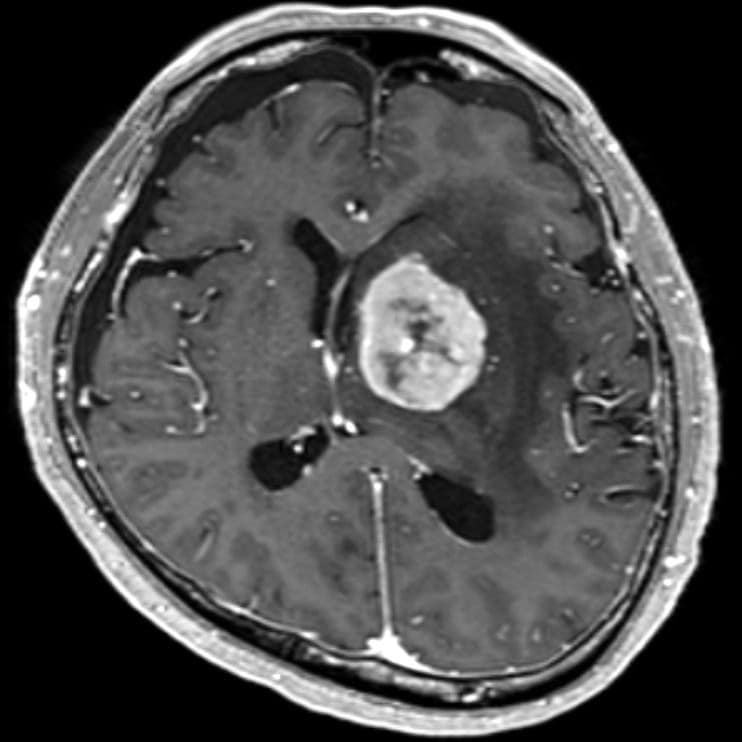

認知機能低下、行動異常、右不全片麻痺の進行を認め、頭蓋内の精査目的に頭部MRIが施行された。左大脳基底核に腫瘍性病変および腫瘍周囲浮腫の所見を認めた。同病変は、造影T1強調像画像では極めて淡い軽度の造影効果を示し、拡散強調画像では軽度の高信号、ADC画像では低信号を示した。診断確定のため生検手術を行った。生検手術1週間後に頭部MRIを施行すると、術前に施行した頭部MRIとは所見が変化し、左大脳基底核の病変は造影T1強調画像では明瞭な造影効果を認め、拡散強調画像でも高信号の増強、ADC画像では低信号を示した。病理組織学的診断は中枢神経系原発悪性リンパ腫であった。そのためR-MPV療法(リツキシマブ、メトトレキサート、プロカルバジン、ビンクリスチン)を施行した。R-MPV療法の経過中の頭部MRIでは、左大脳基底核の病変は縮小傾向を認め、それに伴い初診時に認めていた認知機能低下、行動異常、右不全片麻痺は改善傾向にあり、良好に経過している。

中枢神経系原発悪性リンパ腫(PCNSL)についても造影T1強調画像では、高率に均一な強い増強効果を示すとされている*2。しかし本症例のように、初診時は造影所見をほとんど認めず、生検手術後に明瞭な造影所見を認めるように変化するPCNSLの症例も少数ながら報告されている*2。このように造影所見が変化する主なメカニズムとして以下の4つの機序が考えられる。

非造影PCNSLにおいては、拡散強調画像での高信号やADC値の低下が有用とされているが、画像的診断は困難である場合が多い。そのような症例においては、生検手術によって血液脳関門の破綻・血管新生・免疫応答などの複合機序が作用し、造影所見が明確になることが多いとされている。そのため、非造影PCNSLの診断に関しては、生検手術のタイミングと術後造影MRIの再検査による統合的評価が重要である。